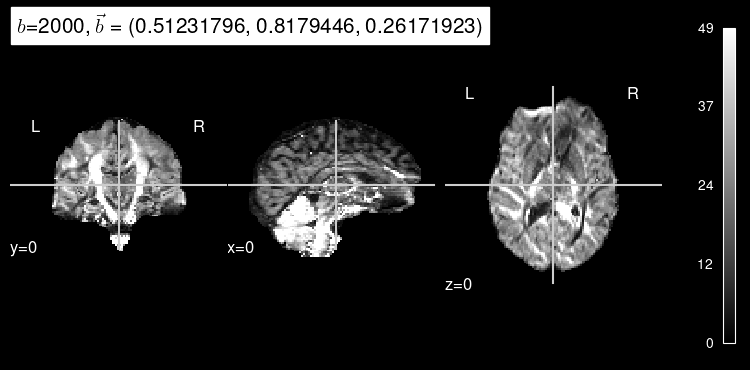

Now, the predicted map for the particular b gradient looks much closer to the original:

plot_dwi(predicted, dmri_dataset.affine, gradient=data_test[1], black_bg=True);

Here’s the original DW map, for reference:

plot_dwi(np.squeeze(data_test[0]), dmri_dataset.affine, gradient=data_test[1]);